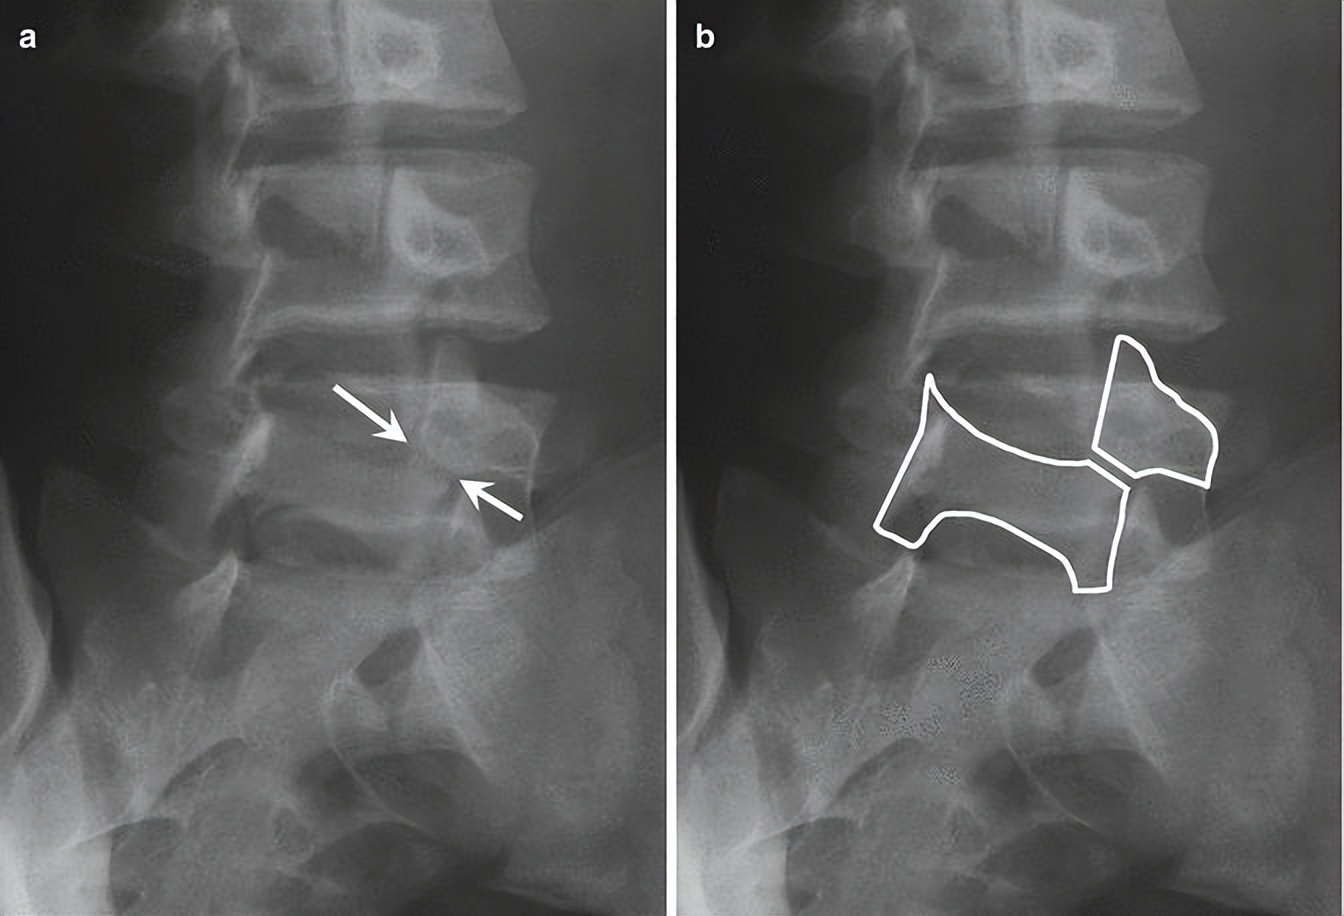

诊断腰椎峡部裂,腰椎双斜位片通常是需要的,表现为“苏格兰狗脖子”断了(见下图)。但对于一些隐匿的患者,腰椎双斜位片是看不出的,这时候需要行腰椎CT、MRI进一步明确诊断,少数部分需行核素骨扫描才能明确诊断。

1. 腰椎峡部和峡部裂在X线斜位片的表现

腰椎峡部在腰椎斜位片上常比喻为苏格兰狗(Scotty dog)的脖子

椎弓崩裂征象:X线腰椎45°斜位摄片示上关节突轮廓似"狗耳",横突似“狗头/嘴”,椎弓根似“狗眼”,下关节突似“狗前肢”,关节突肩部或称峡部似“狗颈部”。椎弓峡部崩裂时,“狗颈部”可见裂隙。

腰椎斜位片上的苏格兰狗和断裂的脖子(峡部裂)